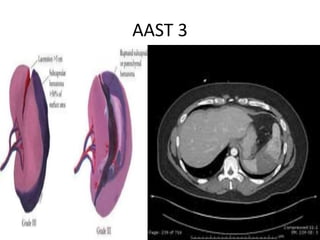

AAST Grading:

AAST 3